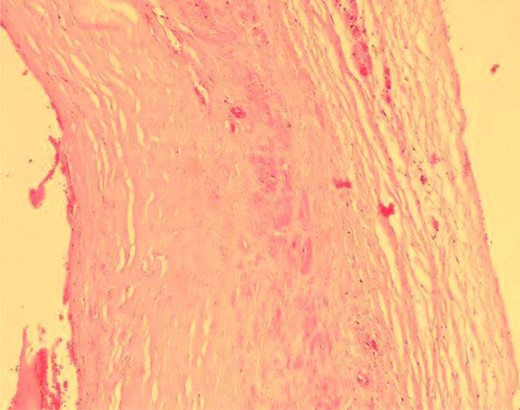

Under local anaesthesia, the aneurysm site was incised. A saccular aneurysm of 2-by-1.5 cm appeared at the distal part of the radial artery. Using vessel loops, the artery was controlled proximal and distal to the aneurysm (Fig. 4). After clamping the artery, a Doppler examination was conducted and indicated positive signals over the thumb and digital arteries. Then, artery ligation followed by aneurysm excision was done. The post-operative period was uneventful. Later, the histopathology report showed a dilated arterial sac with a complete fibromuscular wall and an organized thrombus attached to its lumen (Fig. 5).

Microscopic view of the aneurysmal wall shows the muscular layer.